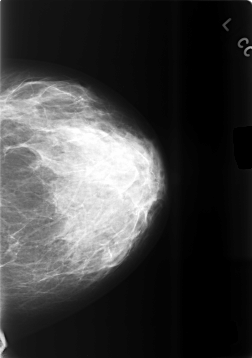

C_0478_1.LEFT_CC

LEFT_CC LINES 5720 PIXELS_PER_LINE 4032 BITS_PER_PIXEL 12 RESOLUTION 50 NON_OVERLAY